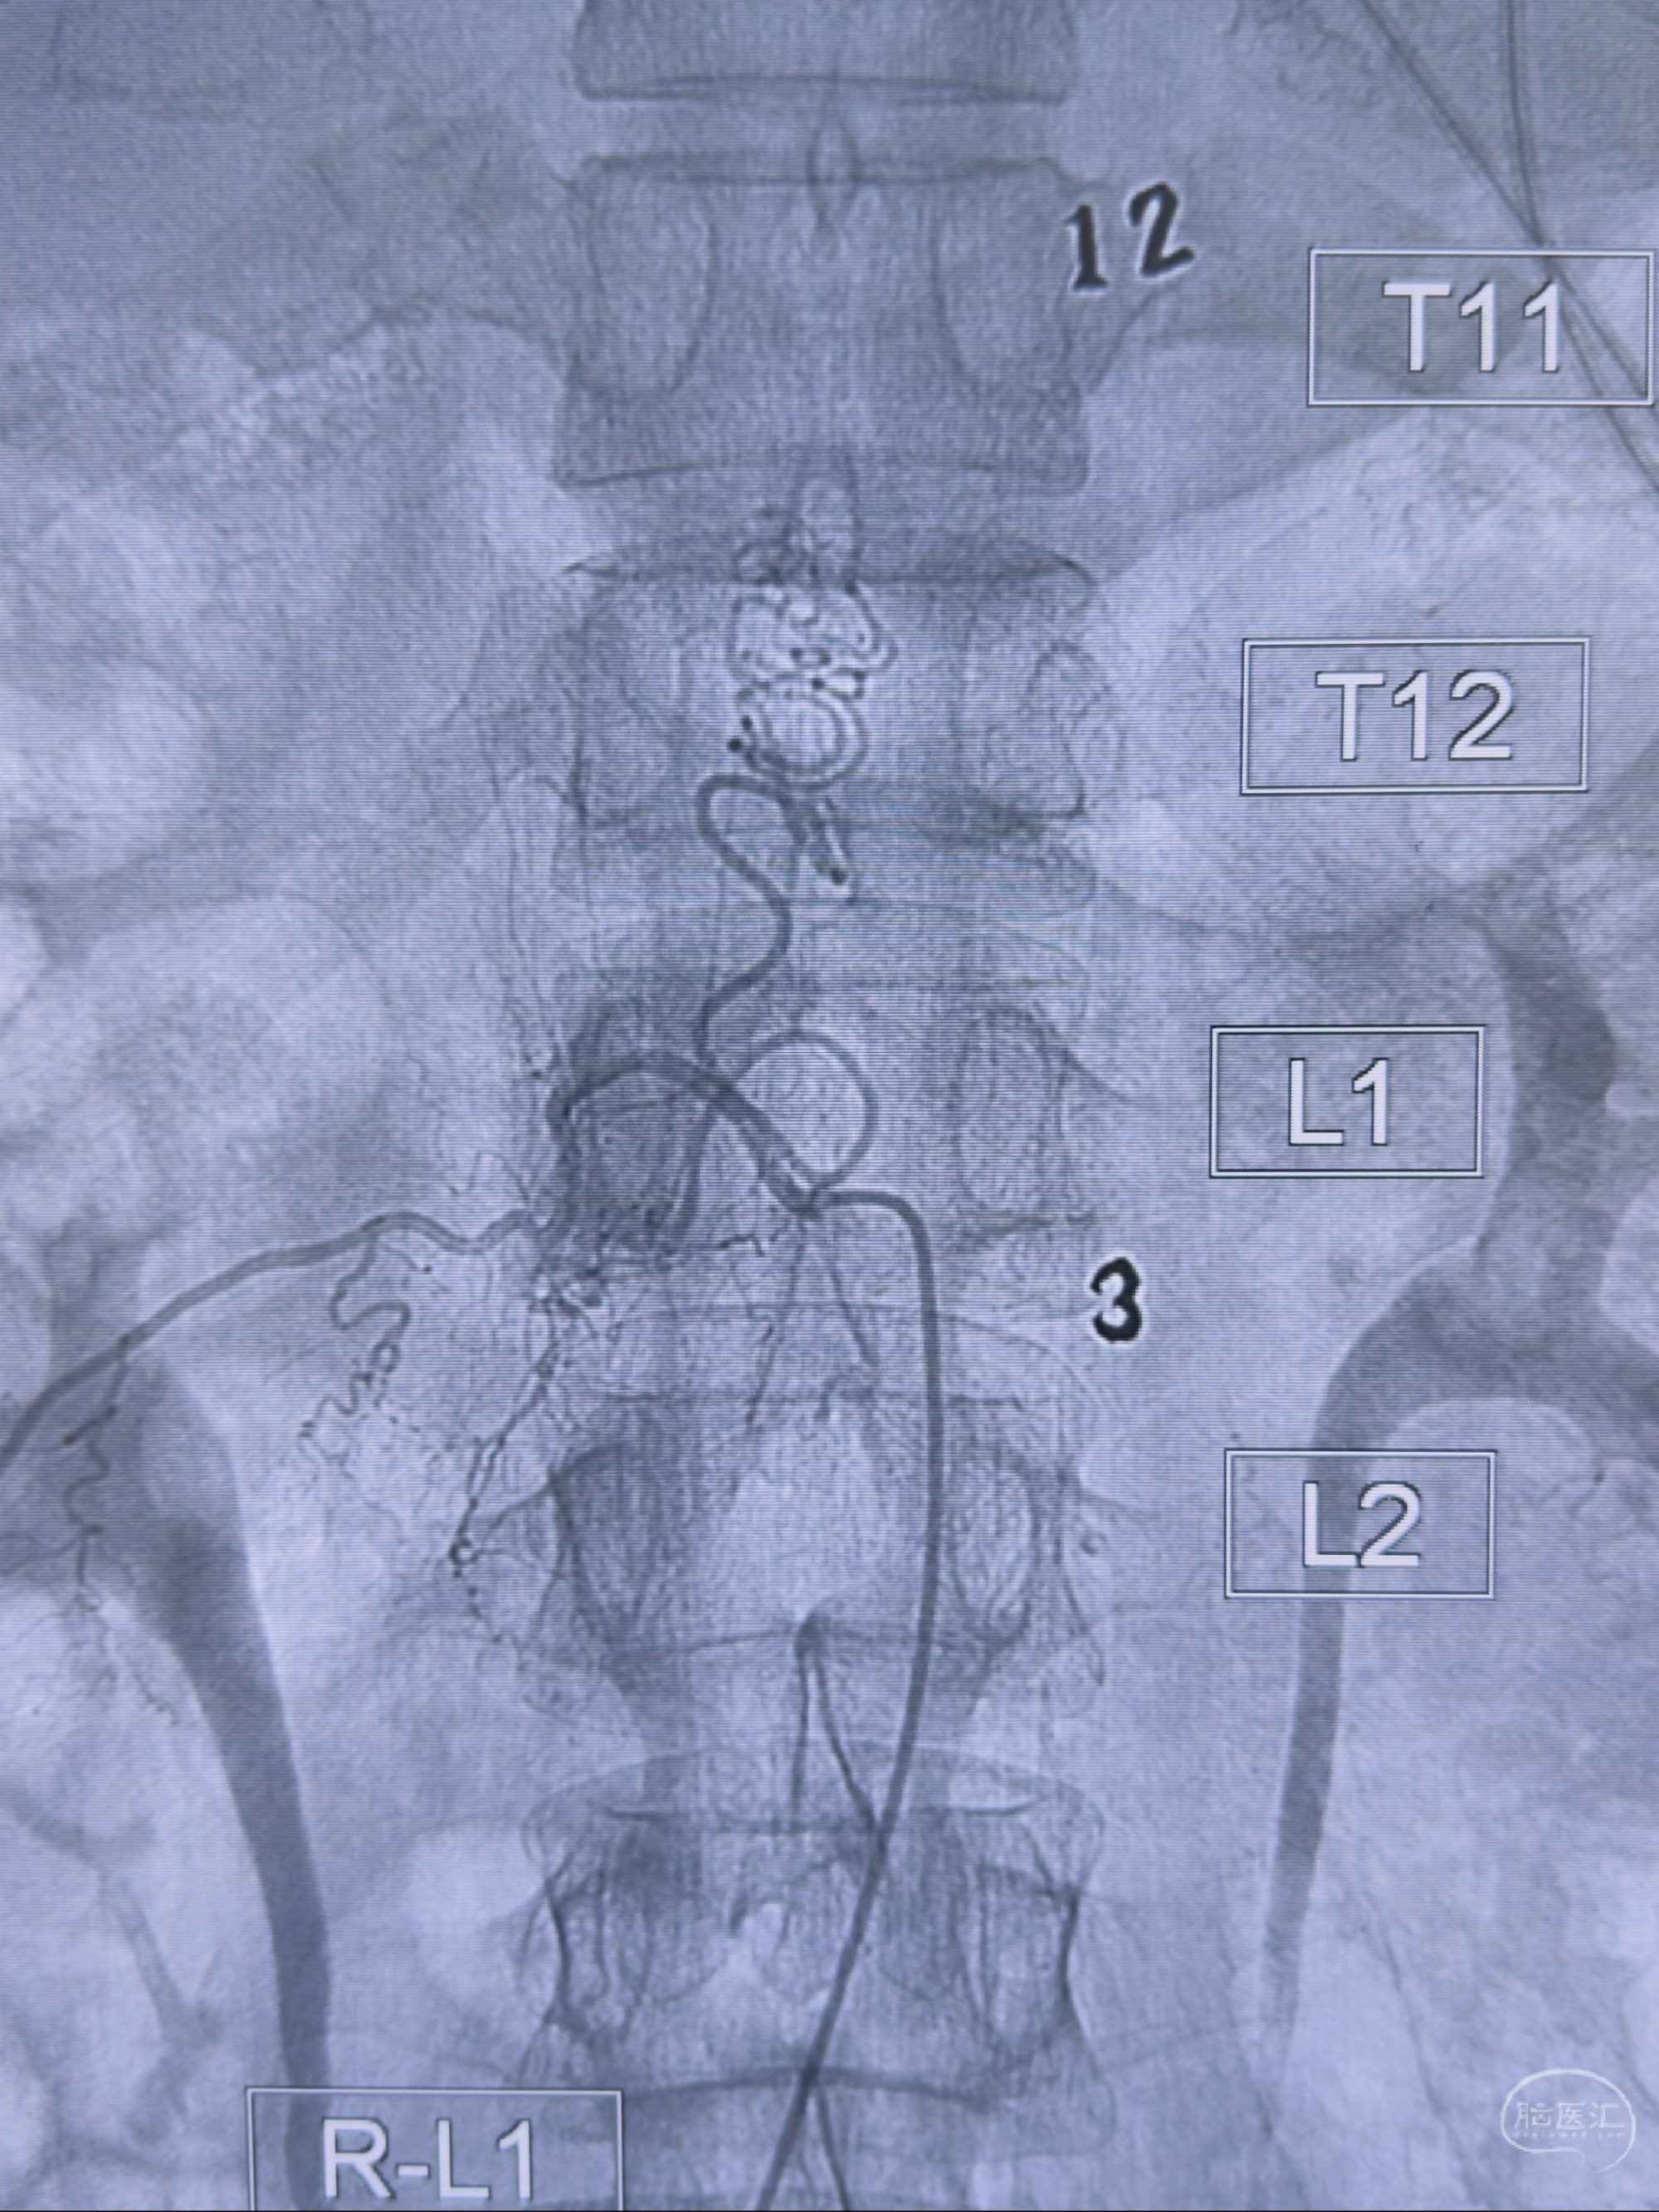

2023-10-13DSA:右侧L1水平硬脊膜动静脉瘘,供血动脉为右侧L1,附近动脉未见明确吻合供血,供血动脉处可见脊髓前动脉发出

1.建议外科手术,已行美兰定位c